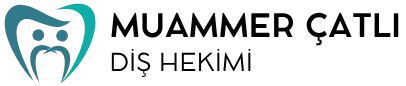

İşlem günü, gerekli diş çekimleri yapılır ve çeneye toplam dört implant yerleştirilir. Arka bölgelerde yer alan implantlar belirli açılarla konumlandırılır. Bu yöntem, kemik grefti ihtiyacını azaltabilir. Tedavinin sonunda geçici bir sabit protez yerleştirilir. Böylece hasta aynı gün içerisinde konuşabilir, gülebilir ve temel çiğneme fonksiyonlarını kazanabilir.

- Dört implantın uygun açılarla yerleştirilmesi

Yaklaşık 3–4 ay sonra implantların kaynaşmasıyla birlikte kalıcı sabit protez uygulanır. Bu süreçte ağız ve diş sağlığının korunması, implantın başarılı şekilde iyileşmesine katkı sağlar. Diş yüzeylerinde oluşan plak birikimini önlemek için düzenli temizlik önemlidir.